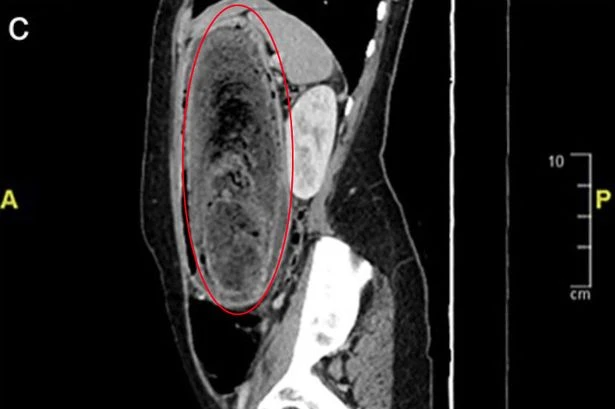

Horrified medics pull giant hairball out of 17-year-old 'Rapunzel's' stomach